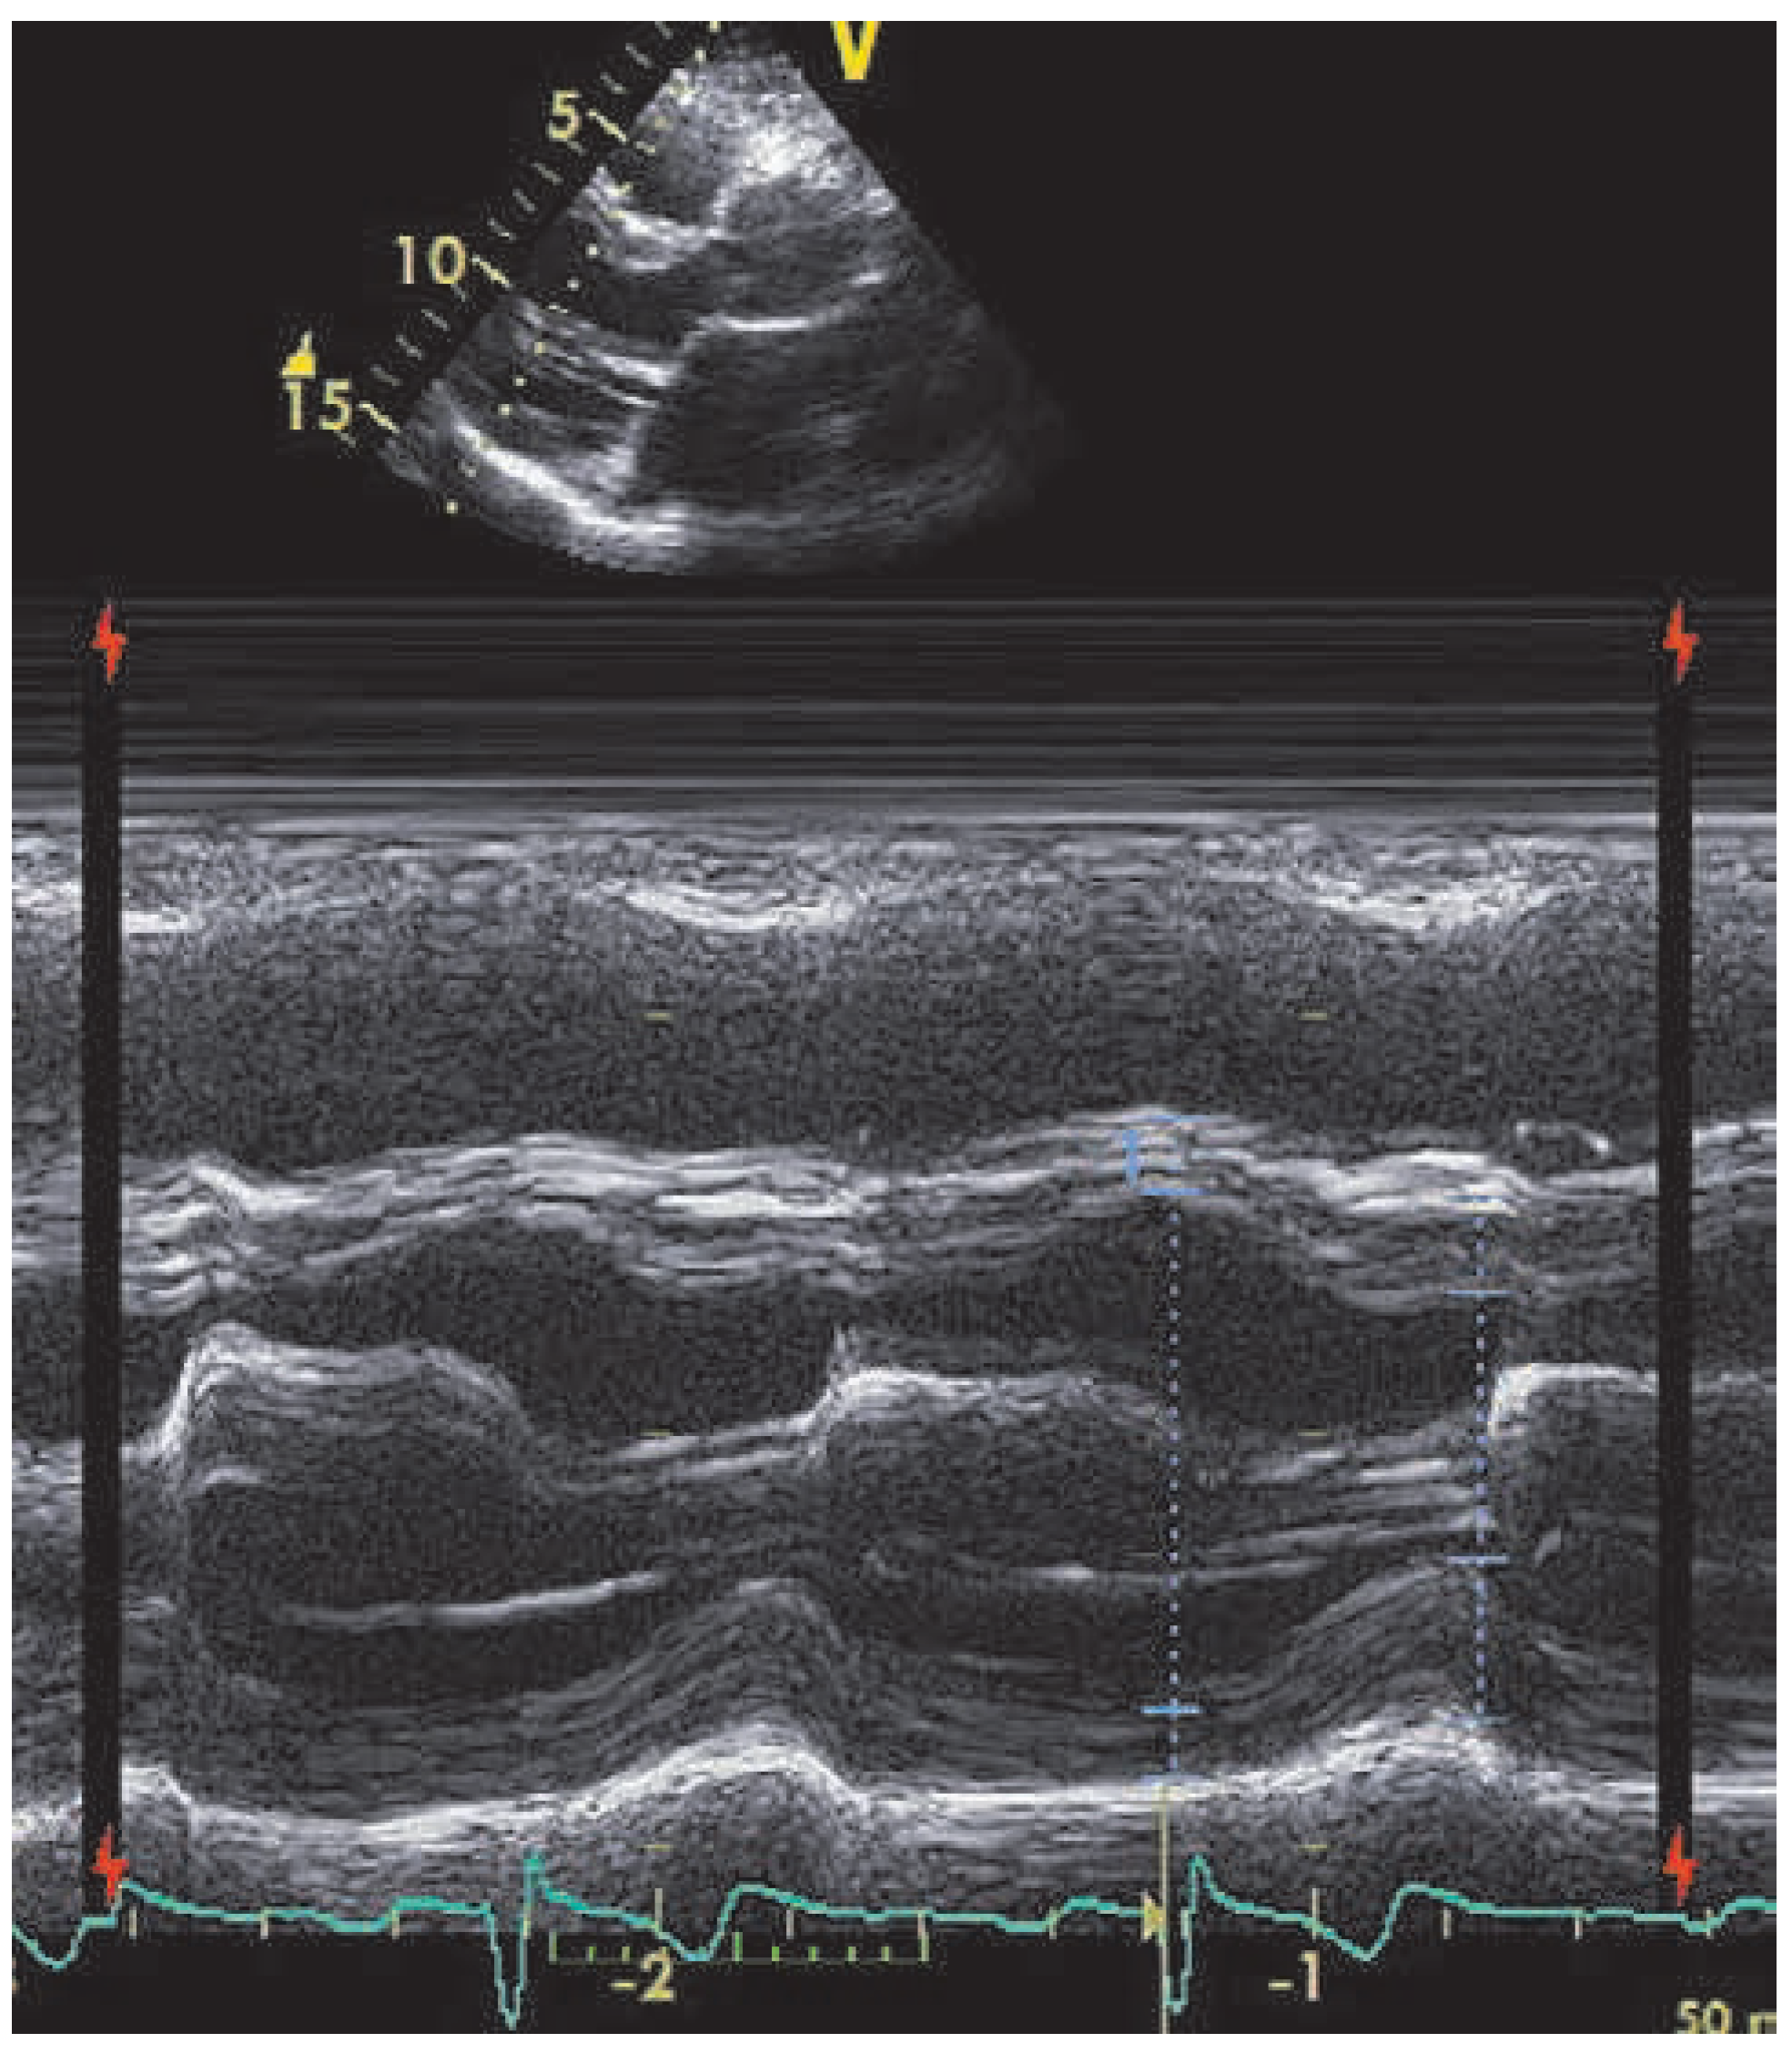

A 59-year-old man was referred to our institution for dyspnea. He had a history of mitral valve regurgitation with posterior leaflet valve prolapse. In 2006 he underwent mitral repair without annuloplasty ring implantation. In April 2012 dyspnea, NYHA II–III, recurred. Echocardiography showed grade III to IV mitral regurgitation. He was referred to another hospital, where percutaneous treatment with MitraClip™ implantation was proposed to the patient. Two MitraClips™ were implanted. Shortly after the intervention the patient complained about shortness of breath. He was seen at our hospital. Transthoracic echocardiography (Figure 1) and cardiac computed tomography (Figure 2) confirmed the clinical impression of both mitral stenosis and regurgitation with significant gradient and a valve surface of 1.7 cm2. M-mode echocardiography showed typical patterns of mitral stenosis (Figure 3). Mitral valve repair with annuloplasty could be performed with neocordals, reinforcement of the posterior leaflet and ring implantation (Figure 4 and Figure 5). Six months later, the mitral valve is fully functional and the patient is asymptomatic. This case is remarkable for a few points: firstly, mitral annuloplasty with ring implantation should be performed instead of simple repair. Secondly, equivalence of surgery with MitraClip™ implantation has been proven in some trials. However patients included in these studies were older and sicker than our patient. There are more arguments to suggest that MitraClip™ should be reserved for nonoperable patients or to patients refusing surgery. In our patient, revision surgery was probably a better option than a percutaneous approach. Valve dysfunction requiring a second intervention is almost 10 times more frequent after MitraClip™ implantation than after conventional surgery. Thirdly, even though trials about MitraClip™ are still ongoing, indications should not be lifted to younger patients, until we have clear evidence regarding the comparison of the 2 techniques. Finally, mitral valve repair with annuloplasty and ring implantation is possible after MitraClip™ implantation.

Figure 3. M-mode image with typical patterns of mitral stenoses.